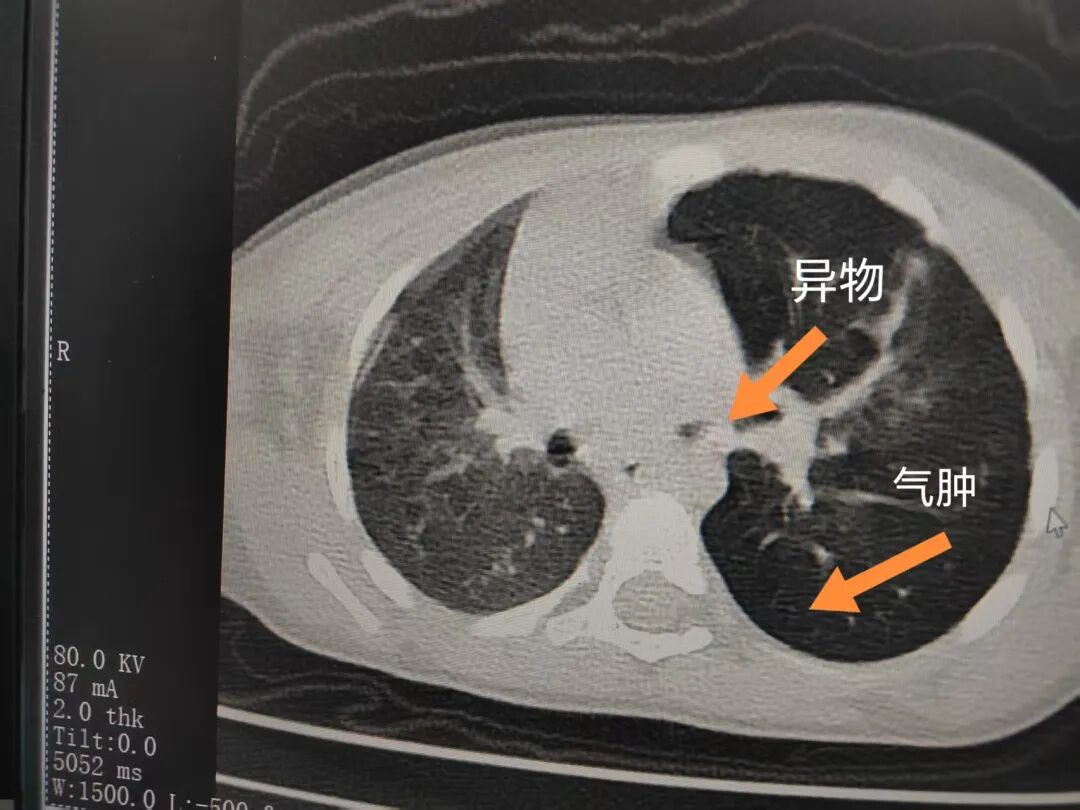

三天后(11月13日),趙寶出現(xiàn)高熱、咳喘加重,家長(zhǎng)著急了,再次帶他來(lái)到醫(yī)院。CT檢查顯示左肺過(guò)度充氣,左肺上下葉支氣管主干見不規(guī)則高密度影,左肺上葉可見大片狀密度增高影,縱隔窗實(shí)變,提示為“左側(cè)支氣管內(nèi)異物并繼發(fā)性改變,左肺上葉舌段肺膨脹不全”。

市二院小兒呼吸內(nèi)科團(tuán)隊(duì)迅速為患兒制定了周密的手術(shù)方案,并很快安排了氣管鏡探查。術(shù)中,主治醫(yī)師田慧等憑借嫻熟的氣管鏡操作技術(shù)成功將異物大塊板栗取出。由于板栗在氣管內(nèi)存留時(shí)間較長(zhǎng),質(zhì)地軟糯易碎,大大增加了手術(shù)難度。檢查還發(fā)現(xiàn),異物停留部位的氣管黏膜已出現(xiàn)充血紅腫、糜爛,導(dǎo)致患兒住院時(shí)間相應(yīng)延長(zhǎng)。此次事件給趙寶的家庭帶來(lái)了不小的驚嚇與擔(dān)憂,也再次為廣大家長(zhǎng)敲響了警鐘。